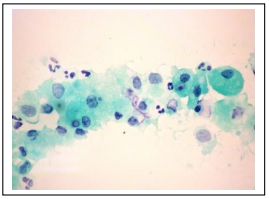

105. A 5-year-old girl, fine needle aspiration for LN: What is the most likely diagnosis?

(A) Birkitt lymphoma (B)Small cell carcinoma (C)Infectious mononucleosis (D)Large cell lymphoma (E)None of the above